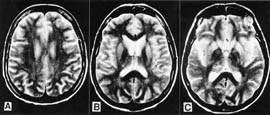

Pasienten. 54 år gammel kvinne. Hun hadde tidligere stort sett vært frisk, men gjennomgikk flere tannekstraksjoner og maksillærkirurgi det siste året før sykdomsdebut. De første symptomene var svimmelhet, asteni og vertigo, som tiltok gradvis. Åtte måneder senere utviklet hun ustø gange, eufori og raskt progredierende demens med desorientering, tap av korttidsminne og visuelle hallusinasjoner. Ved klinisk undersøkelse fant man nystagmus, ataksi, myoklonus, positiv mandibular og palmomental refleks og grav demens. Computertomografi (CT) av hjernen og blodprøver viste normale funn. EEG viste diffus dysrytmi med generalisert theta- og deltaaktivitet, men de typiske periodiske skarpe bølger som vanligvis sees ved Creutzfeldt-Jakobs sykdom, var ikke til stede. T2-vektet MR av hjernen viste ingen definitive avvik (fig 1). Diffusjonsvektet MR av hjernen viste markert økt signaldensitet, dvs. redusert diffusjon bilateralt i corpus striatum og gyrus cinguli (fig 2). Hun døde etter en måned i koma, 15 måneder etter debuten av de første symptomene. Diagnosen ble postmortalt bekreftet med utbredte, typisk spongiforme encefalopatifunn ved den histopatologiske undersøkelsen (fig 3). Prionproteingenanalyse viste ingen mutasjoner, men hun var homozygot for valin/valin i codon 129 (utført ved Creutzfeldt-Jakob Disease Surveillance Unit, Edinburgh, Skottland).

Diagnostikken av Creutzfeldt-Jakobs sykdom er ofte vanskelig. Sikker diagnose krever histopatologi. Cerebrospinalvæskeanalyse er ofte normal, men forhøyet nevronspesifikk enolase eller 14-3-3-hjerneprotein er blitt rapportert i noen tilfeller. EEG viser ikke spesifikke funn i alle tilfeller. CT av hjernen er vanligvis normal og viser kun atrofi hos 20 % av pasientene (14). Vanlig MR-undersøkelse (T2 er inkludert) av hjernen viser symmetriske hyperintense forandringer i basale ganglier i 80 % av tilfellene (7), men disse forandringene er vanligvis beskjedne og uspesifikke for Creutzfeldt-Jakobs sykdom (15).